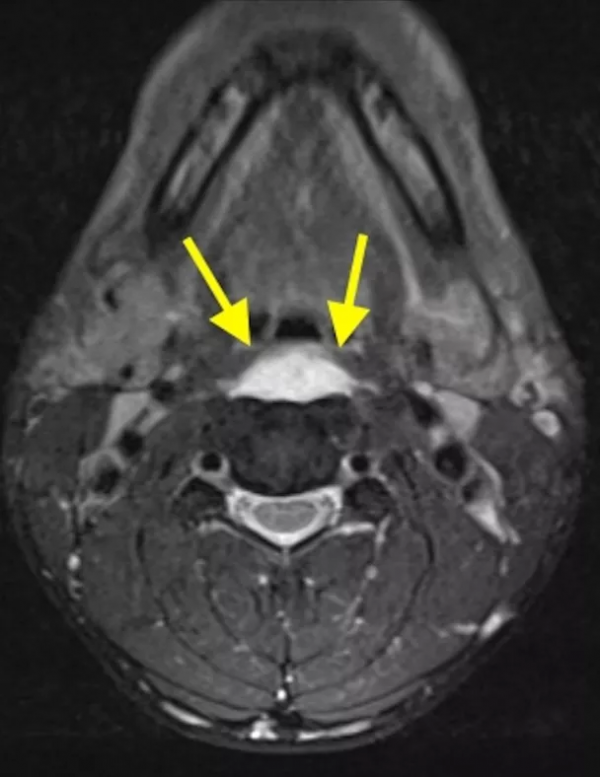

典型病例介紹

36歲女性,急性頸痛、吞嚥困難伴頸部僵硬,MRI示C1-2前部頸長肌增厚呈低訊號,提示鈣化(長箭頭)和C1-4椎前積液(無線箭頭),經類固醇和止痛藥治療8天后症狀消失,複查MRI提示上述表現消失。(PMID: 18765656)

C1-2前側低訊號(無線箭頭)和C1-5椎前水腫(長箭頭) (PMID: 19567634)